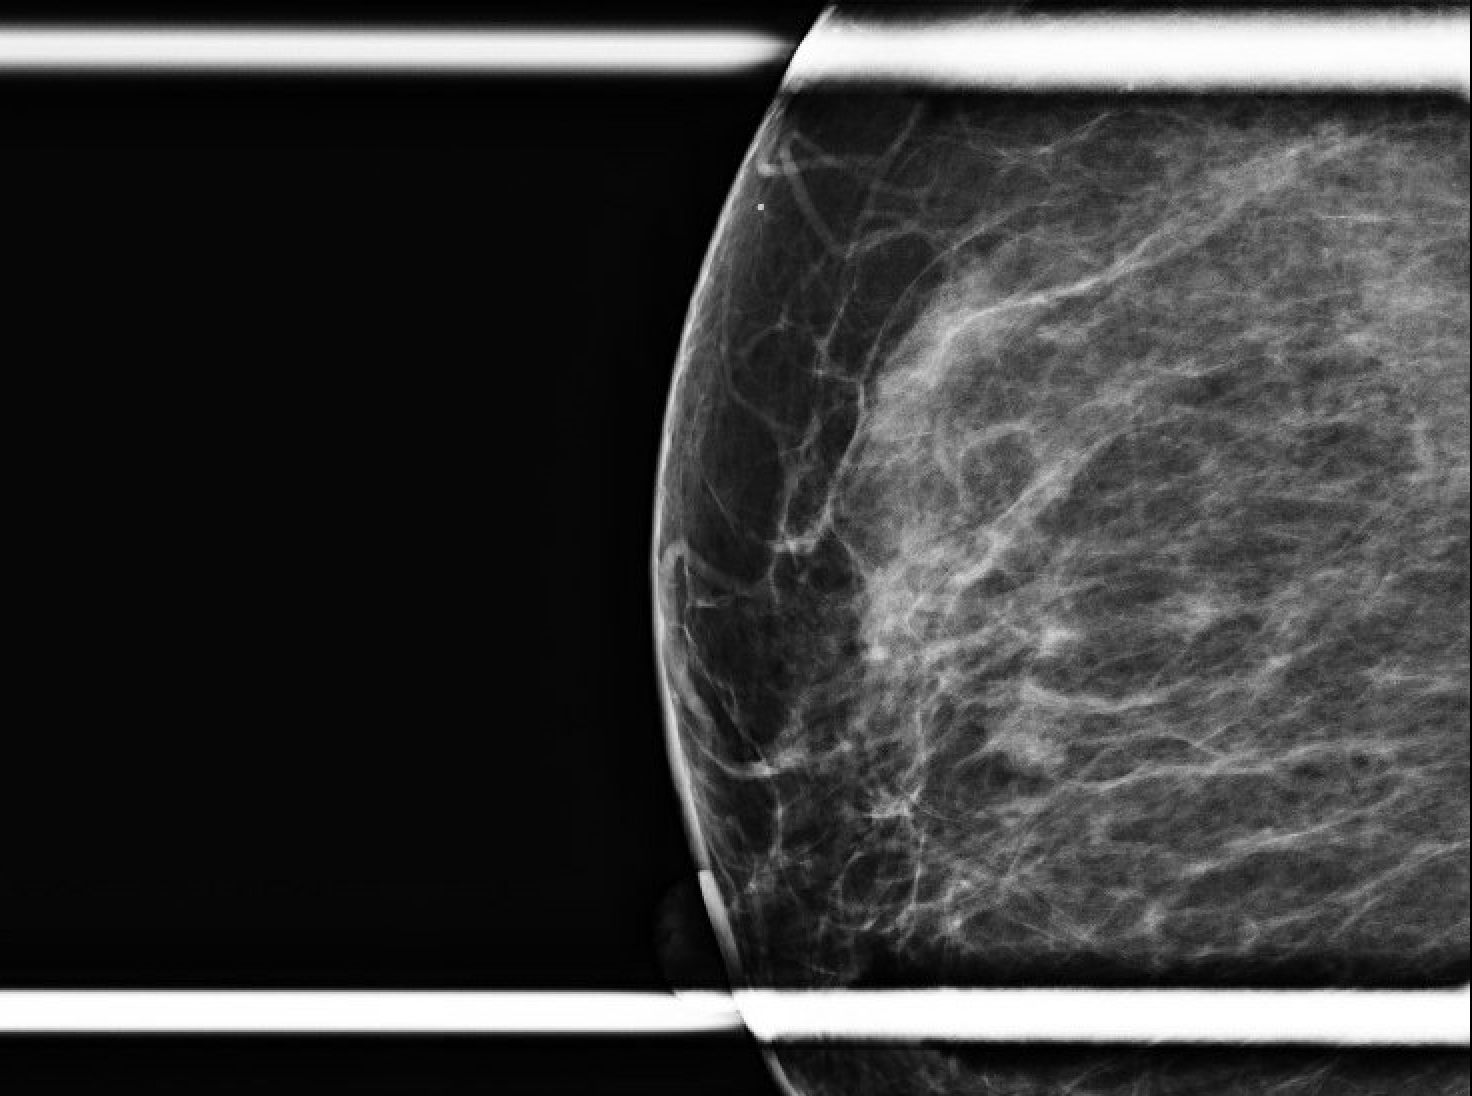

Se trata de una mujer premenopáusica de 46 años, sin antecedentes médicos o quirúrgicos, que acudió inicialmente a la clínica de cirugía mamaria después de que su mamografía anual de cribado descubriera una masa mamaria derecha no palpable de 0,6 x 0,8 x 0,7 cm a las 11 horas (oc), a 1 cm del pezón (FTN) (Figura 1). Se sometió a tres mamografías de detección previas sin ningún hallazgo notable. La mamografía de tamizaje se declaró no concluyente (BI-RADS 0) y se completó una ecografía mamaria con hallazgos similares. Una conversación más detallada con la paciente reveló que se había observado una secreción sanguinolenta en el lado derecho de su sostén en los últimos meses, pero no había otras preocupaciones o síntomas. Ante los hallazgos imagenológicos no concluyentes, se decidió realizar una mamografía diagnóstica para una valoración más específica (Figuras 2a y 2b) tras una biopsia con aguja gruesa guiada por ecografía y la colocación de un clip de localización para el diagnóstico tisular (Figura 3). La anatomía patológica reveló un papiloma intraductal con hiperplasia ductal y una metaplasia apocrina sin atipia. Dada su continua secreción sanguinolenta del pezón, hubo preocupación por posibles células premalignas subyacentes (discutidas más adelante); Por lo tanto, se recomendó que la paciente se sometiera a una mastectomía parcial. La masa permanecía inpalpable; por lo tanto, se colocaría un Savi Scout justo antes de la intervención operativa para ayudar a localizar el área de interés.

Figura 1. Mamografía de cribado inicial (orientación R mediolateral, seguida de craneocaudal). Reveló que el área de cuestión medida tenía un tamaño aproximado de 0,6 x 0,8 x 0,7 cm, ubicada a 11 oc y 1 cm FTN.